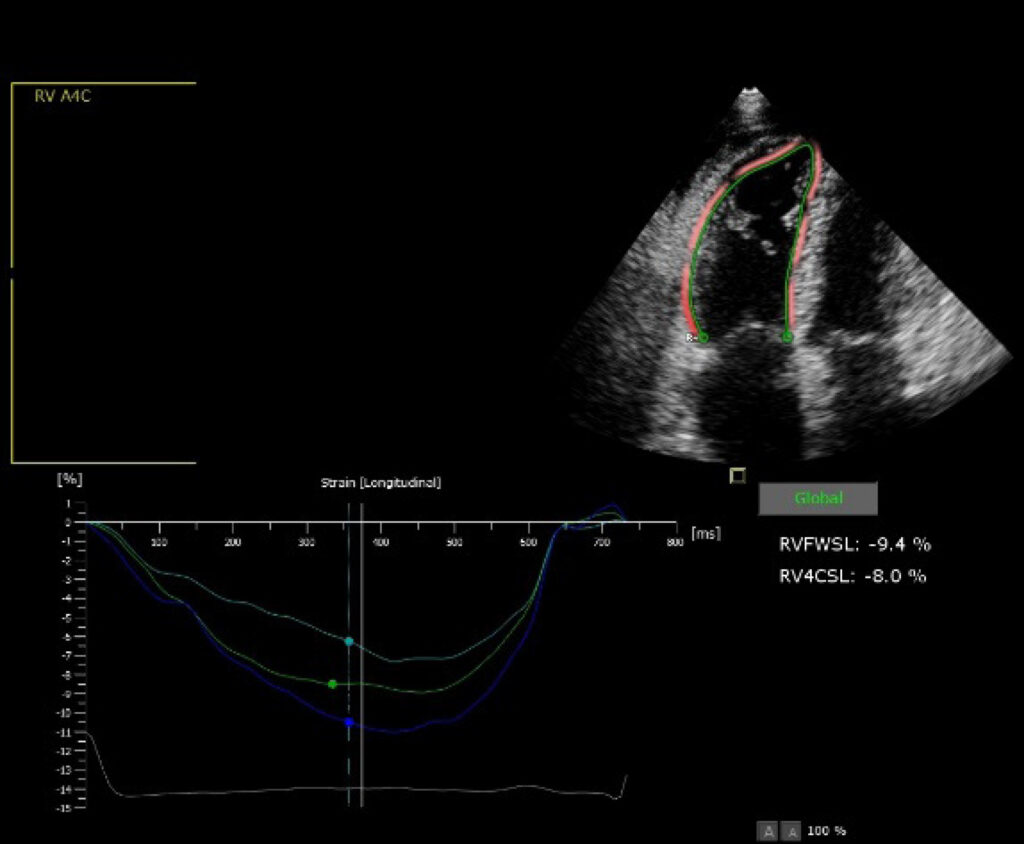

Individuals diagnosed with PH were included. All patients underwent TTE and RCC. The following were evaluated by TTE: right atrial area (RAA), mean right atrial pressure through the diameter and collapsibility of the inferior vena cava (RMAPTTE), RA strain (RAS), tricuspid annular plane systolic excursion, fractional area change, RV free wall strain, and tricuspid s’ wave. Mean RA pressure (RMAPRCC) and cardiac index (CI) were evaluated through the RCC.

Of the 16 patients, 13 were female. The mean patient age was 44.4 (±14.9) years. An association was found between RMAPRCC and AAD, RMAPTTE, and RAS (r=0.845, r=0.621, and r=-0.523, respectively; p<0.05). There was an association between the mortality risk categories measured by the RAA and RMAPRCC measures (X2=10.42; p=0.003), with moderate agreement (k=0.44; p=0.012). RVSDJ was present in 10 patients. There was an association between RVSD (present or absent) and CI (r=0.522; p=0.04) with moderate agreement (k=0.43; p=0.037).